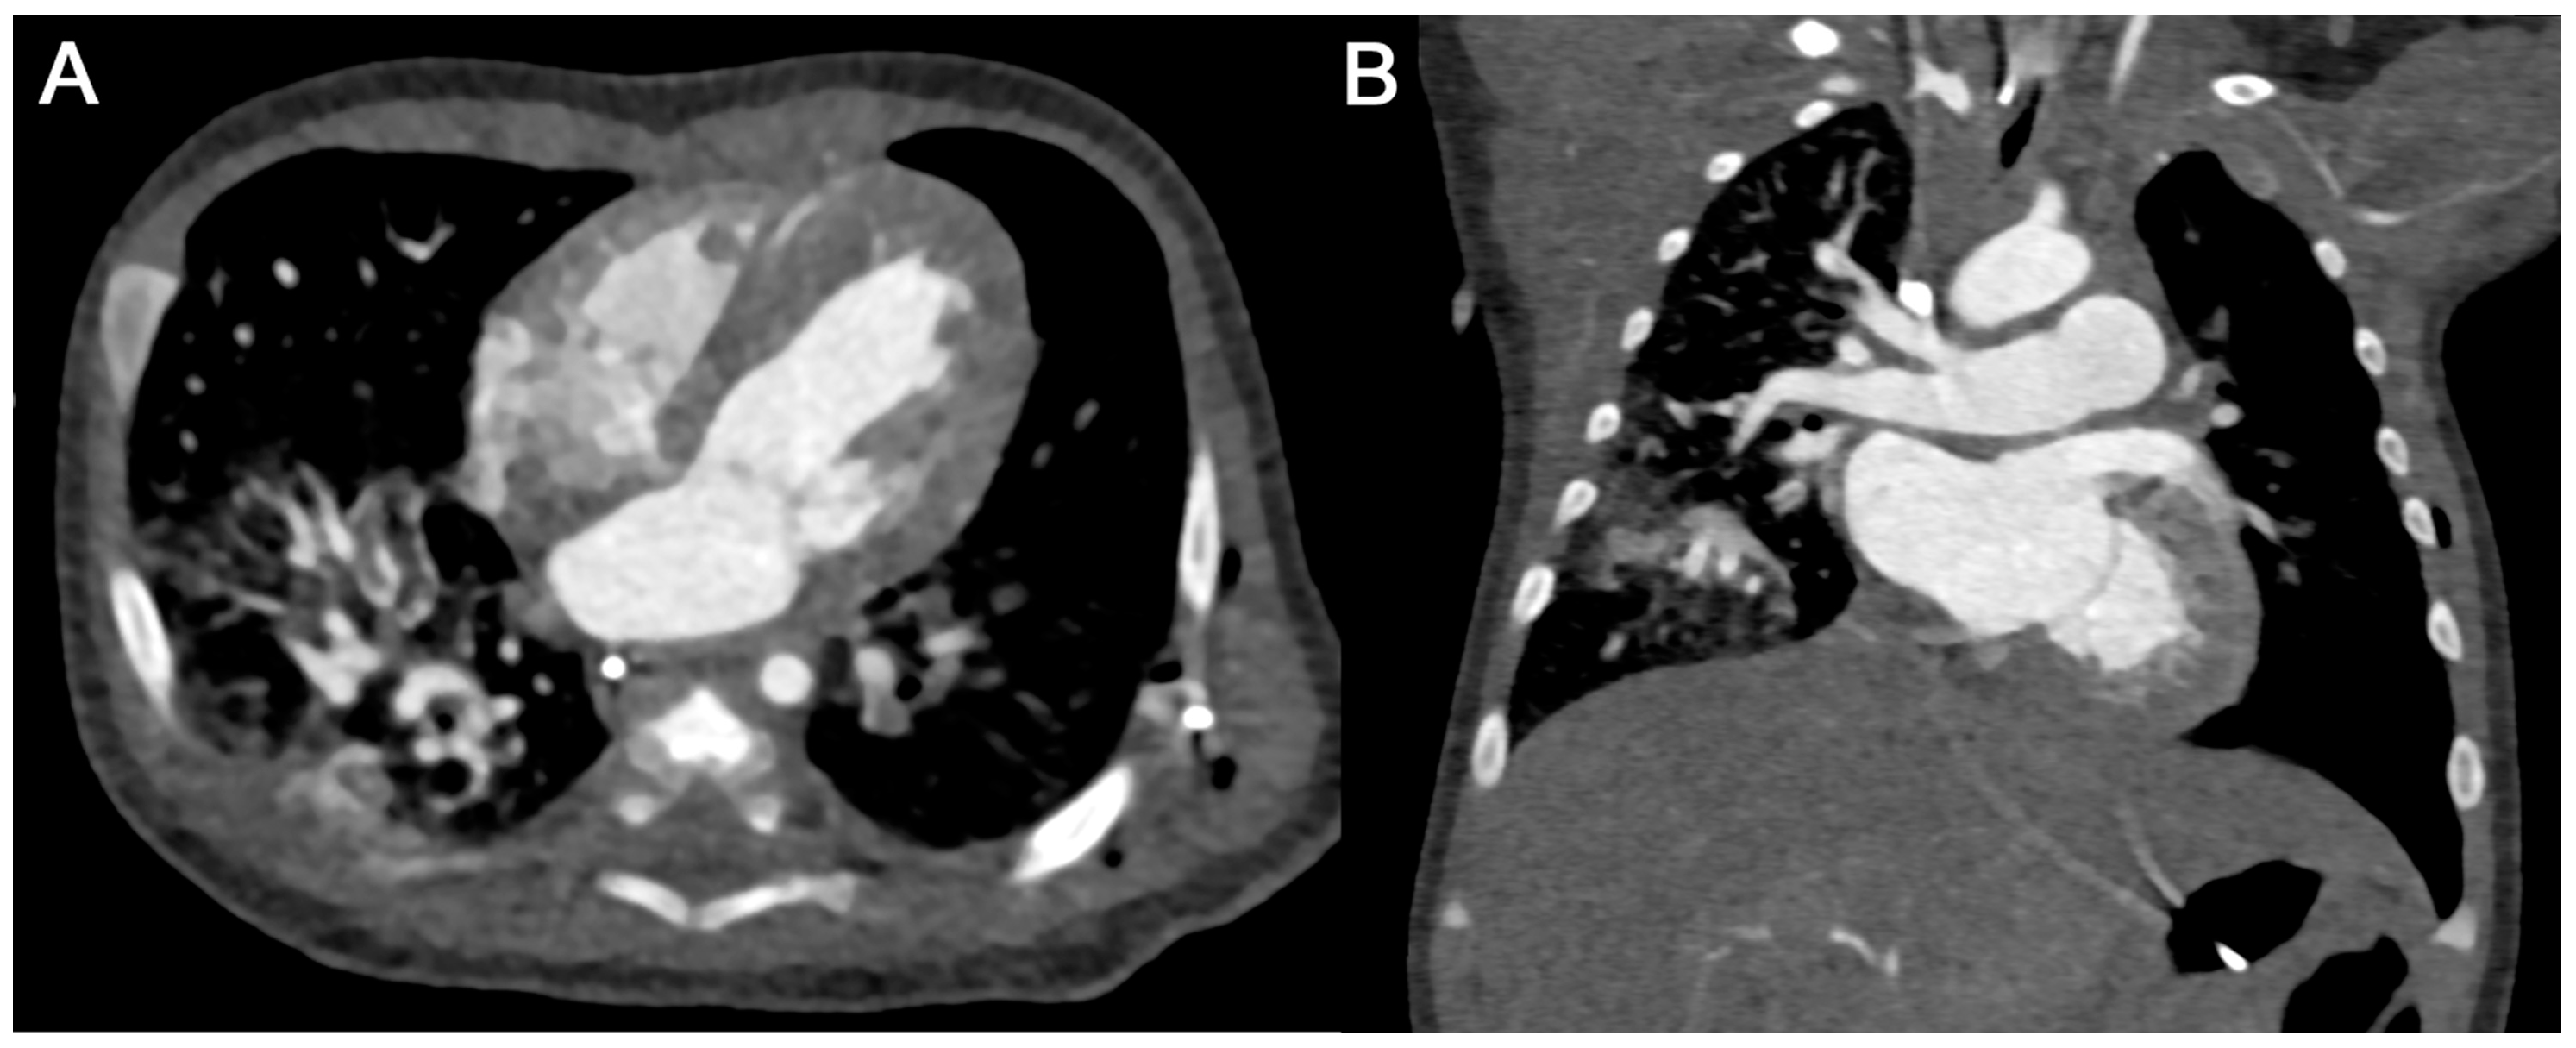

3.3.2. Subjective Image Quality